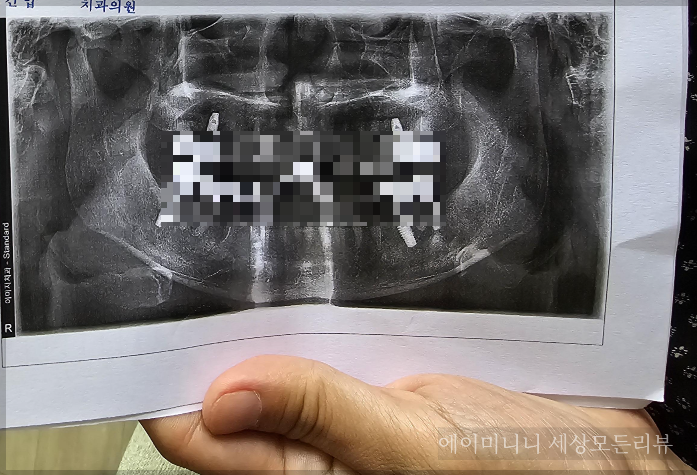

*영구치 발거 전후의 X-ray 또튼 파노라마 사진 또는 이에 준하는 판독자료

치과치료확인서 + 진료차트 + 엑스레이사진